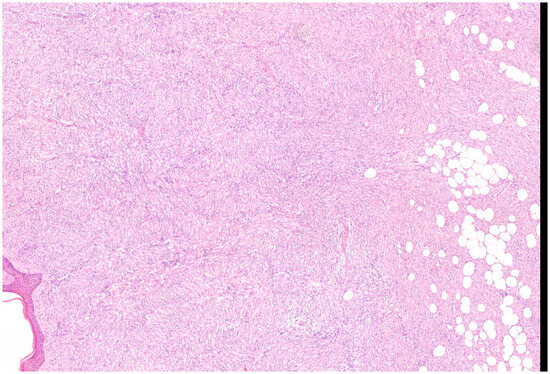

Microscopically, the majority of our cases had the typical aspect of DFSP, presenting as low to intermediate differentiated tumours composed of spindle cells embedded in a collagenous stroma; in 3/69 cases (4.3%), the stroma was described as myxoid. In DFSP, tumour cells are typically arranged in a storiform pattern and show the entrapment of subcutaneous adipose tissue with a sparing of adnexal structures (“honeycomb” pattern). The cytoplasm is scant, eosinophilic, and fibrillary; the nuclei have low-grade atypia and low mitotic activity (Figure 2 and Figure 3). The presence of higher nuclear pleomorphism and increased mitotic count indicates the presence of fibrosarcomatous transformation (DFSP-FS) and was reported in 9/69 cases (13%) [11].

Figure 2. Representative case of vulvar DFSP. Spindle cell proliferation infiltrates the dermis at full thickness and permeates the subcutis, saving some lobules of adipocytes (Haematoxylin–Eosin; 50×).